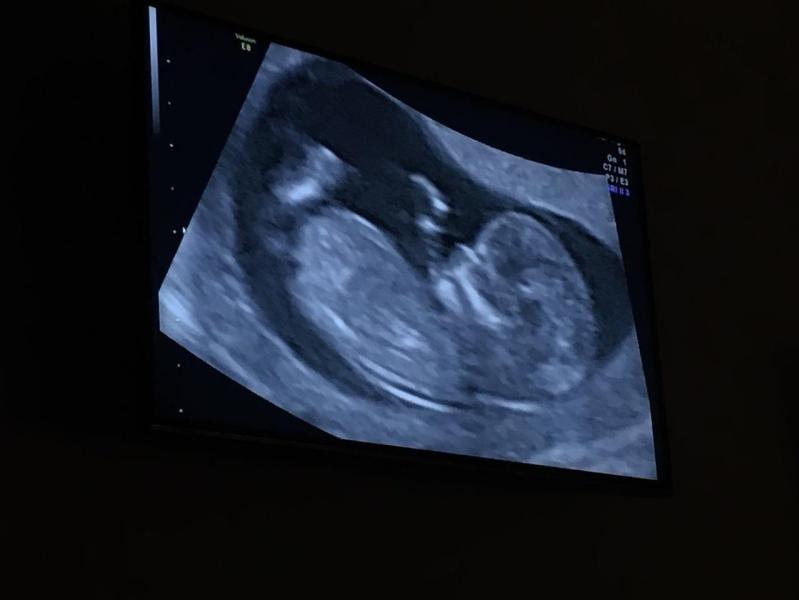

Прошли мы сегодня 3 скрининг 😌

Ровно 32 недели поставили

ПДР 1.01.20

Вес 1730

Плацента поднялась на 8 ,7 см от внутреннего зева)

2 степень зрелости

Все вроде в норме ,все потоки прослушиваются

Показала нам кулак и отвернулась 😄❤️